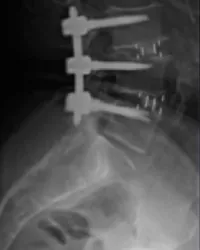

- Instabilités et malformations de la colonne : spondylolyse, spondylolisthésis dégénératif, fracture vertébrale, tassements vertébraux, malformations congénitales (sauf scolioses)…

- Tumeurs rachidiennes : tumeurs vertébrales malignes, métastases vertébrales, tumeurs médullaires, méningiomes rachidiens, neurinomes rachidiens…